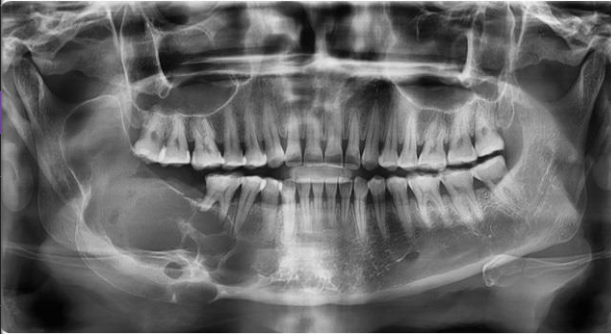

radiographic tendencies (not diagnostic)

abscess-PDL widening, diffuse borders

granuloma-small, well defined RL

cyst-larger, may show corticated border